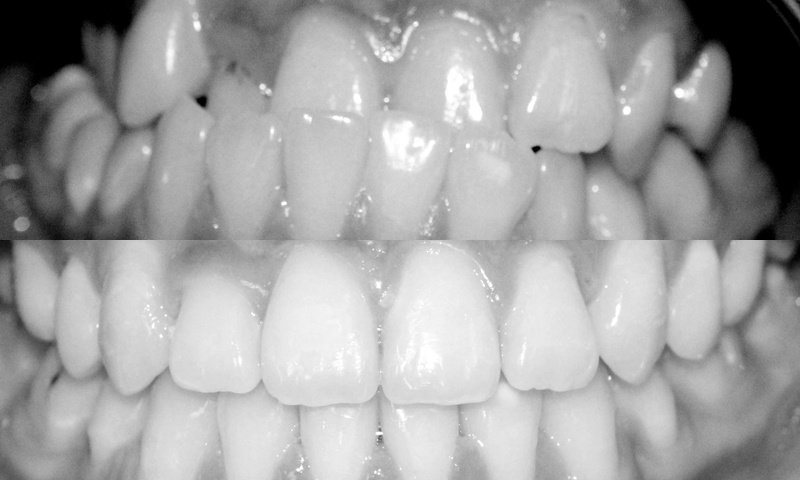

Ví dụ sau đây mà minh chứng:

![]() |

| Bệnh nhân nữ 20 tuổi cũng bị móm, điều trị chỉnh nha trong 25 tháng. |